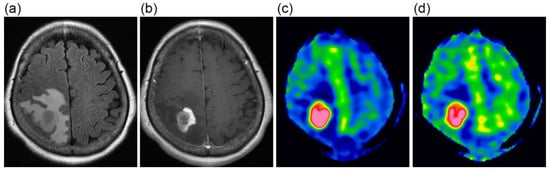

The CBF images obtained at PLDs of 1525 and 2525 ms are exemplified in Figure 1. When mean values of blood flow estimates were compared, neither tumor blood flow, parenchymal blood flow, nor normalized tumor blood flow differed significantly between 1.5 T and 3 T (Figure 2). Moreover, no significant differences were found between PLDs of 1525 and 2525 ms in these blood flow estimates, irrespective of the data analyzed, i.e., data of 1.5 T, those of 3 T, or all data.

Figure 1. A 63-year-old female with glioblastoma. FLAIR (a) and contrast-enhanced T1-weighted (b) images show a heterogeneously enhanced mass lesion surrounded by extensive peritumoral edema. CBF images at 1525 ms (c) and 2525 ms (d), presented using the same display window, demonstrate high blood flow in the lesion.